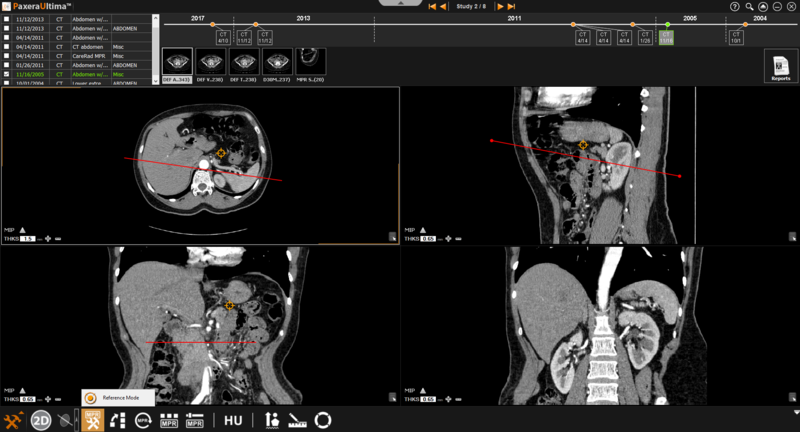

» Reference mode - this is used when the user needs to refer to a specific point (rather than a specific plane)